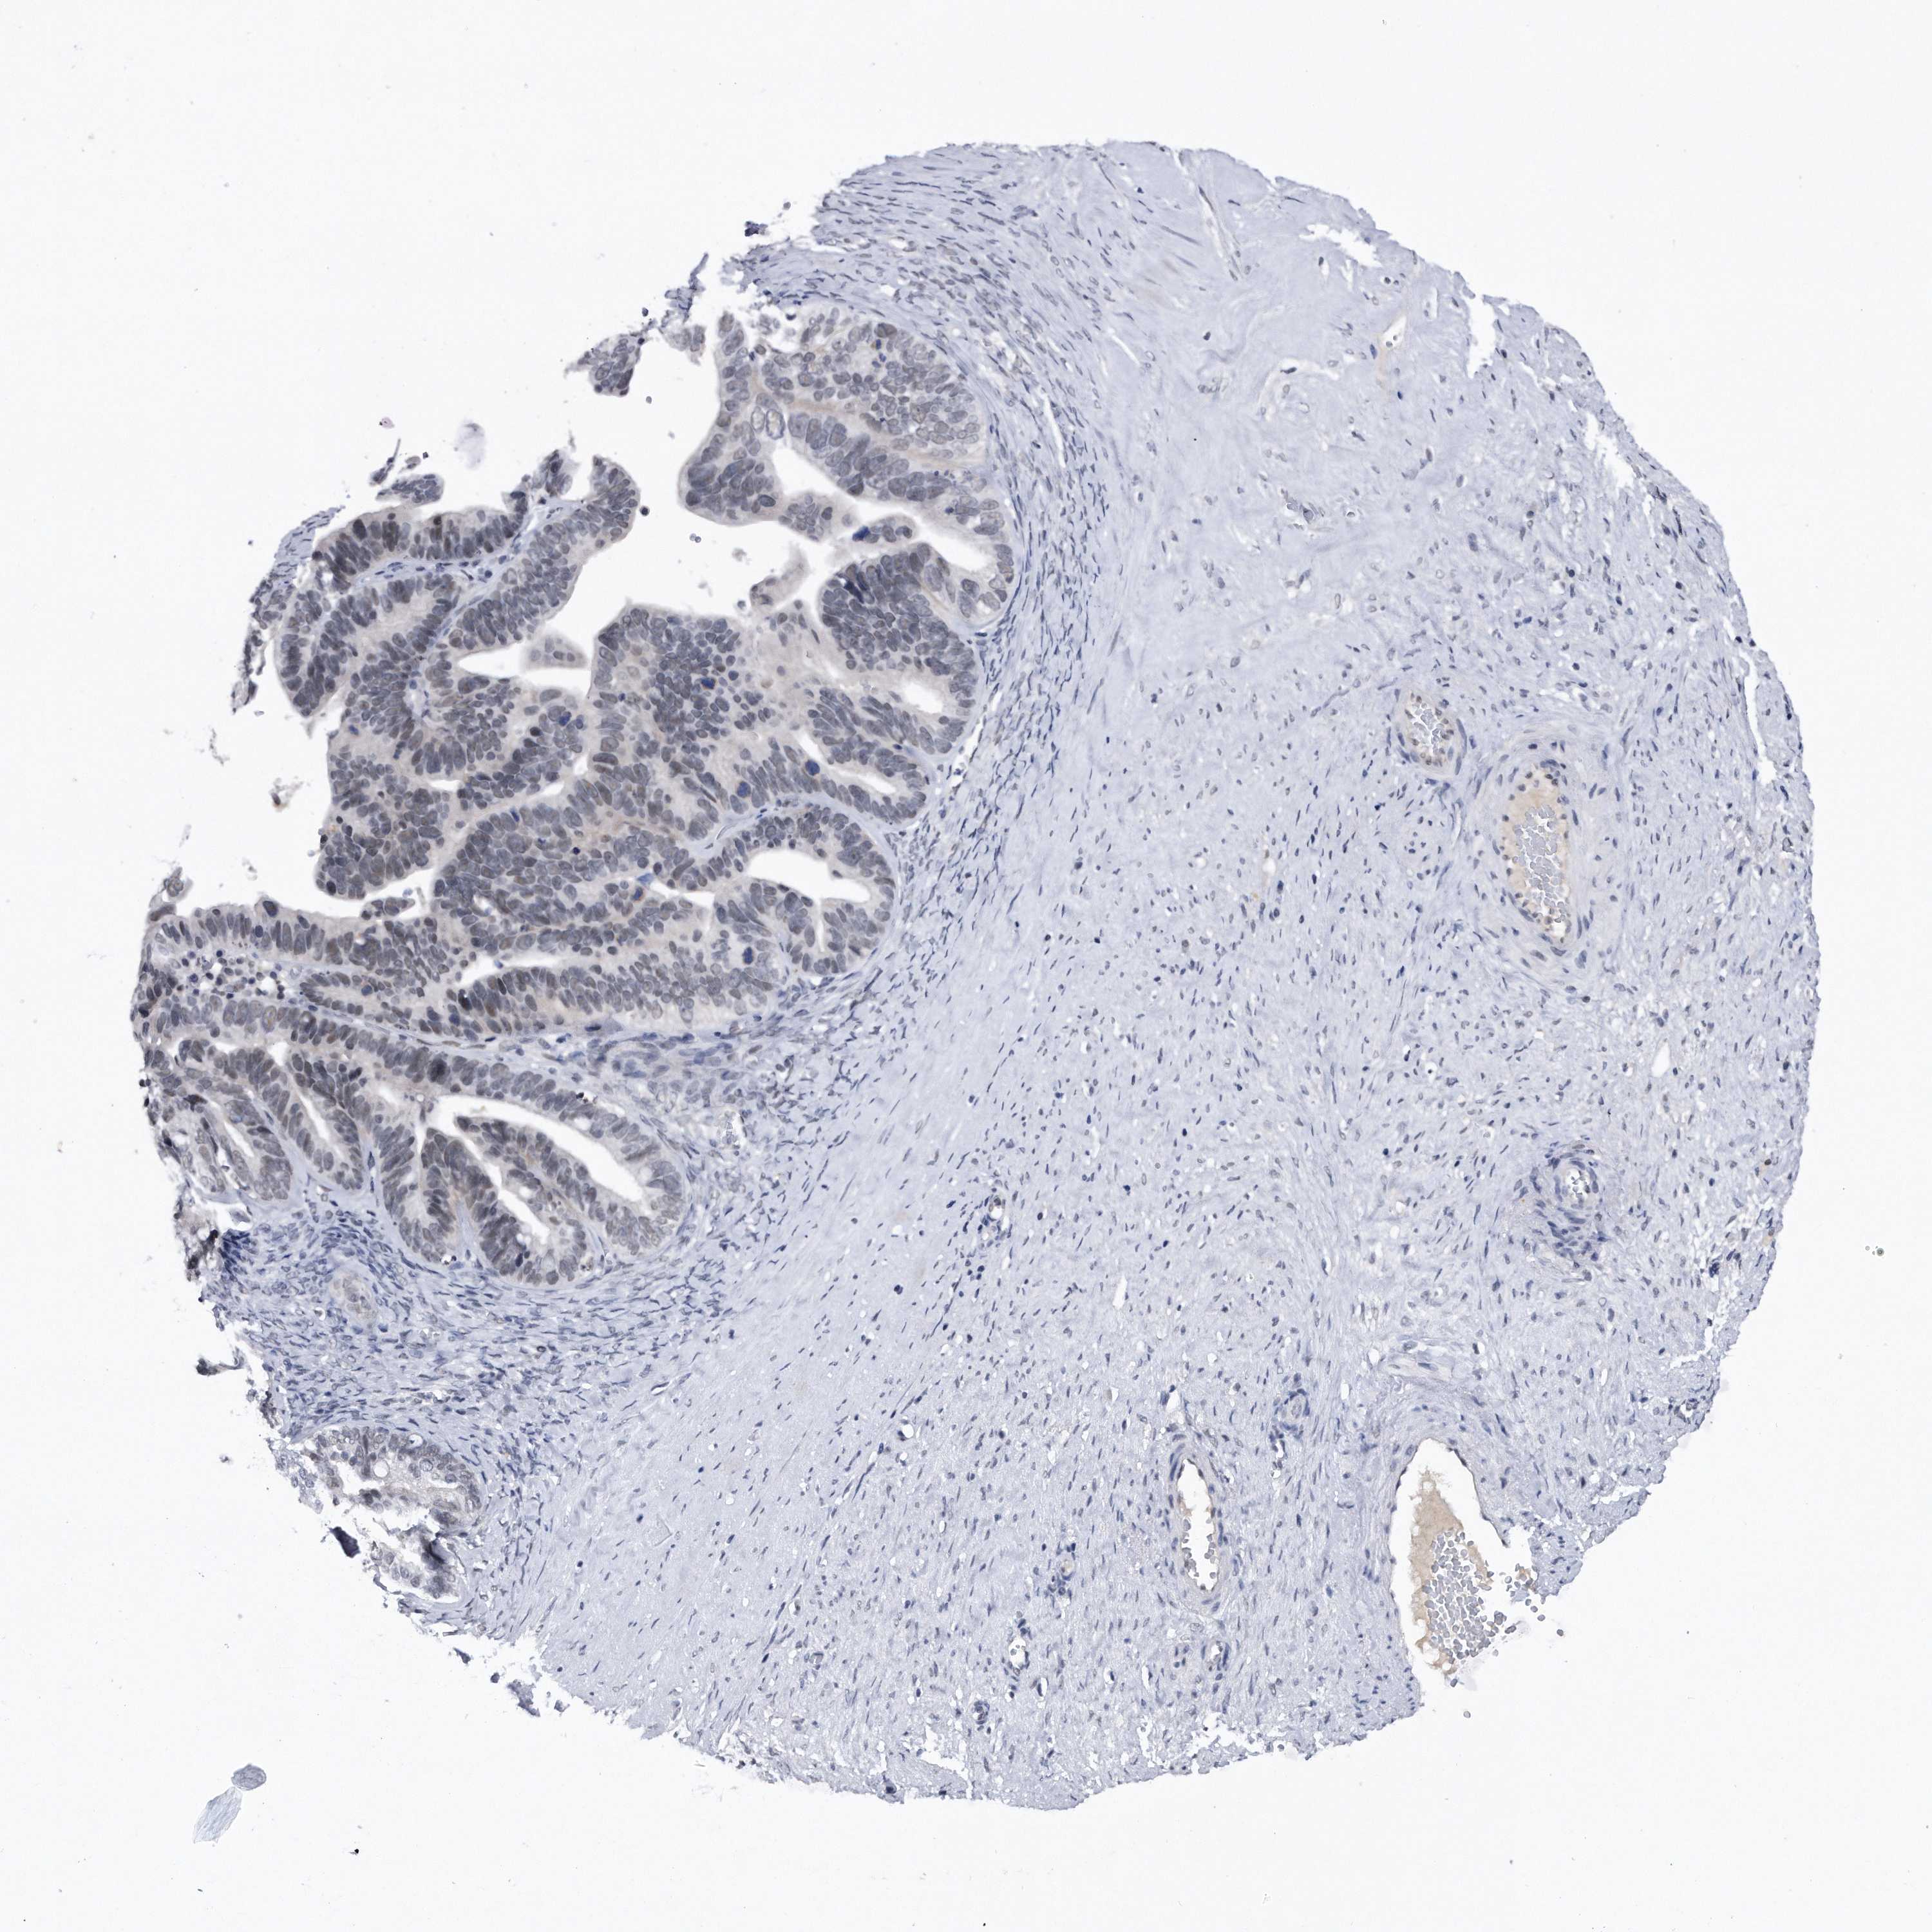

OVARIAN CANCER - Protein expressioni

A mouse-over function shows sample information and annotation data. Click on an image to view it in a full screen mode. Samples can be filtered based on level of antibody staining by selecting one or several of the following categories: high, medium, low and not detected. The assay and annotation is described here.

Note that samples used for immunohistochemistry by the Human Protein Atlas do not correspond to samples in the TCGA dataset.

Antibody stainingi

Antibody staining in the annotated cell types in the current human tissue is reported as not detected, low, medium, or high, based on conventional immunohistochemistry profiling in selected tissues. This score is based on the combination of the staining intensity and fraction of stained cells.

Each image is clickable and will lead to virtual microscopy that enables deeper exploration of all samples and also displays staining intensity scores, fraction scores and subcellular localization as well as patient and tissue information for each sample.

Antibody HPA031530

Staining

High

Medium

Low

Not detected

Intensity

Strong

Moderate

Weak

Negative

Quantity

>75%

75%-25%

<25%

None

Location

Nuclear

Cytoplasmic/membranous

Cytoplasmic/membranous,nuclear

Cystadenocarcinoma, serous, NOS

Carcinoma, endometroid

Cystadenocarcinoma, mucinous, NOS

Carcinoma, NOS